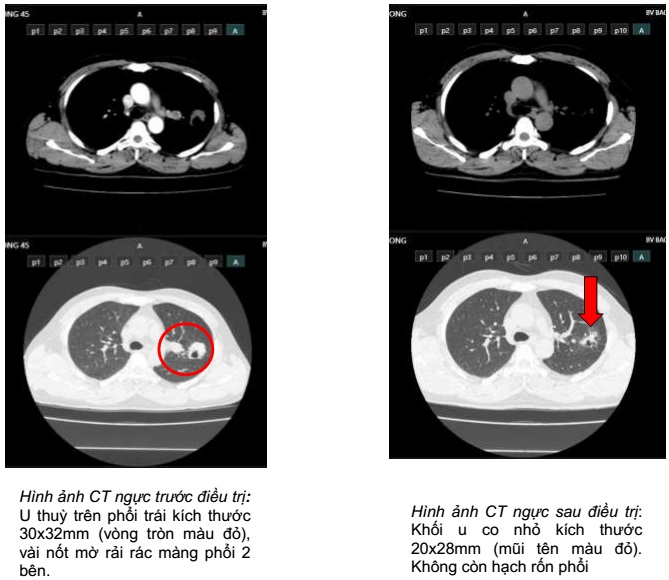

So sánh hình ảnh cắt lớp vi tính ngực trước và sau điều trị 3 tháng

Hình ảnh CT ngực sau 9 tháng điều trị: Khối u phổi phải tiếp tục giảm kích thước 16x19mm (mũi tên màu trắng). Không còn hạch rốn phổi.